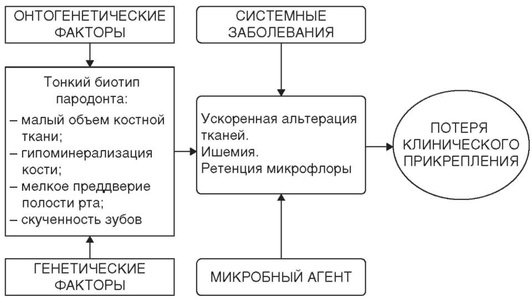

К формированию тонкого биотипа пародонта предрасполагают некоторые генетические и онтогенетические факторы (рис. 4-11).

Рис. 4-11. Факторы, предрасполагающие к формированию тонкого биотипа пародонта

Для тонкого биотипа характерны клинические признаки, способствующие воспалительной деструкции тканей пародонта: малый объем костной ткани и ее гипоминерализация (остеопения) способствуют ускоренной альтерации, мелкое преддверие полости рта формирует локальную ишемию и, так же как и скученность зубов, способствует ретенции и росту микрофлоры. Неблагоприятные анатомо-физиологические особенности при тонком биотипе, относительное увеличение количества пародонтопатогенных микроорганизмов в комплексе с возможным отягощением системной патологией приводят к воспалительной деструкции тканей пародонта, потере клинического прикрепления и формированию рецессий десны.